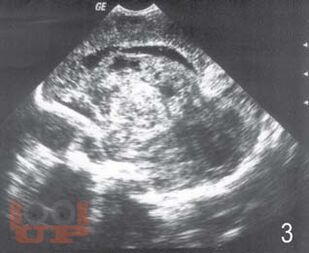

Монография посвящена вопросам ранней диагностики формирования тяжелых структурных постгипоксических изменений мозга у новорожденных детей с помощью определения в крови концентрации нейроспецифических белков, фактора роста сосудов, молекулы клеточной адгезии и маркера апоптоза в раннем периоде постнатальной адаптации. Перед педиатрами и неврологами, занимающимися новорожденными высокого риска всегда встает вопрос: разовьется ли у ребенка внутрижелудочковое кровоизлияние или перивентрикулярная лейкомаляция? Что лежит в основе таких изменений? Результаты, полученные в исследовании, позволили во многом расширить понимание патогенеза постгипоксических изменений головного мозга у новорожденных, а также выделить факторы, которые возможно применять в диагностике патологических процессов в ткани мозга как маркеры. Книга предназначена для детских неврологов, неонатологов, педиатров.